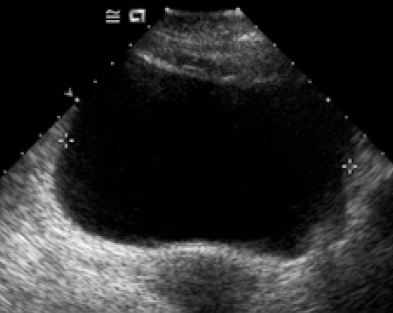

A 17-year-old boy was referred from emergency for ultrasound scanning of abdomen because of vomiting and generalized abdominal pain mainly in the periumbical region of short duration.There was no history of fever and no sign of peritonitis. The routine abdominal scanning using a 3-3.5 MHz probe was inconclusive. Another attempt using a high-density multifrequency linear probe of 5-10 MHz showed an entirely striking picture. There was brighter tubular shadow having an average diameter of 4 mm with a central hypoechoic core (Fig. 1). A cross-sectional view of the worm typical bright ring shadow(Fig 2).. These structural features were consistent with the diagnosis of intestinal ascariasis. The other visceral echoes were normal.

Fig. 1 : A longitudinal section of segment of Ascaris lumbricoides shows the tubular shadow with brighter parallel walls (strip sign). The core is hypoechoic(inner tube sign). The patient's bowel walls are also identifiable